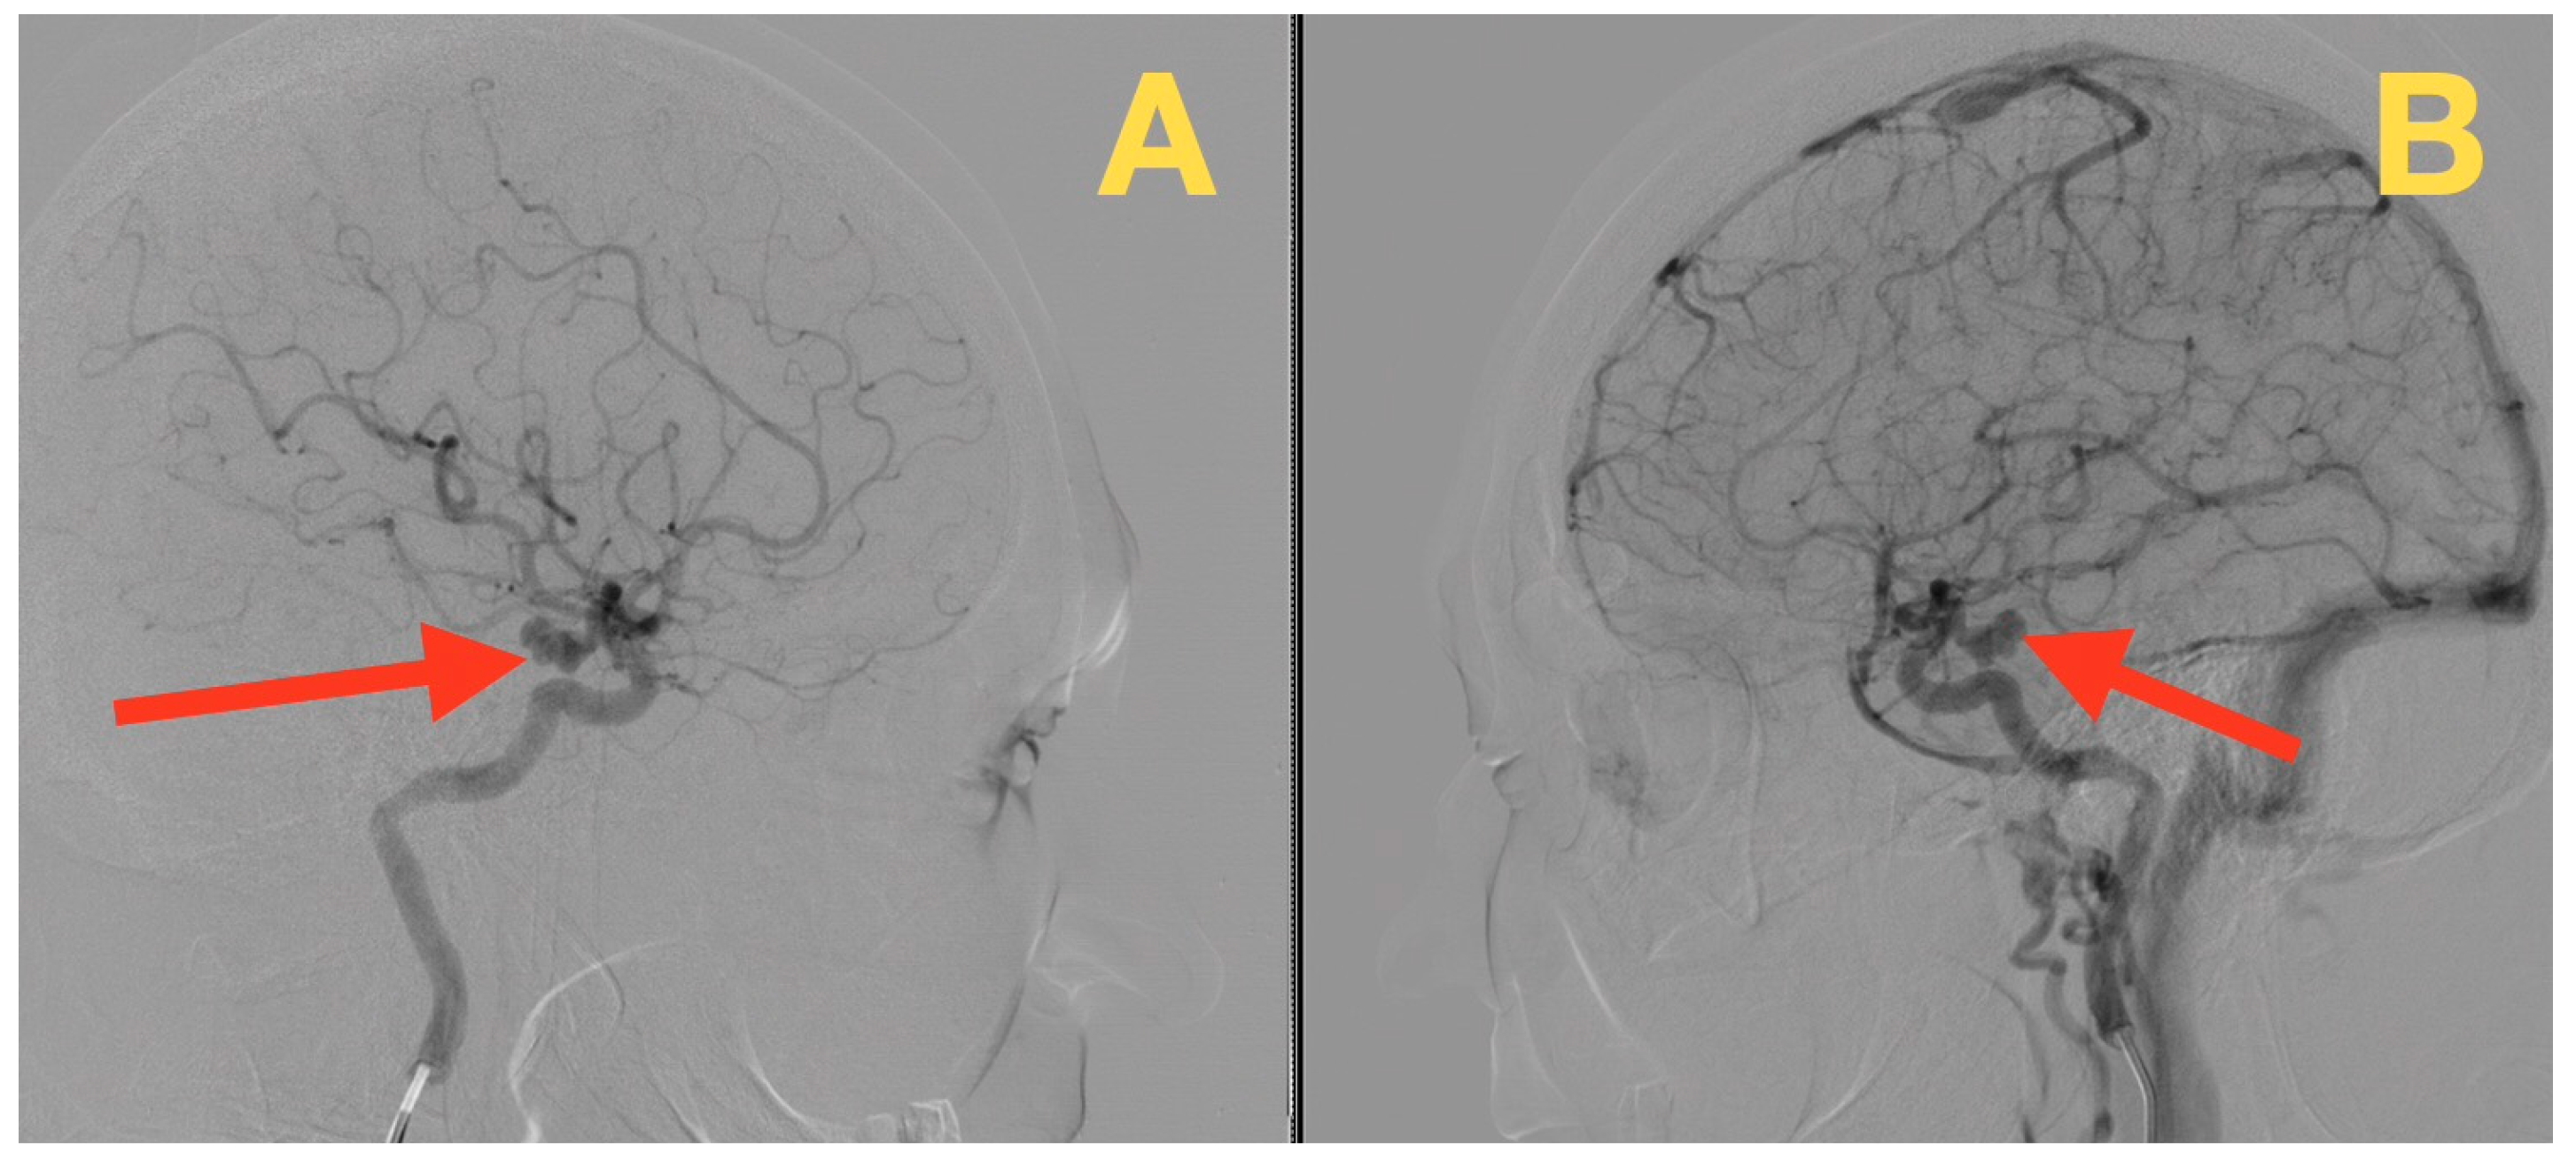

A Ruptured Tri-Lobulated ICA–PCom Aneurysm Presenting with Preserved Neurological Function: Case Report and Clinical–Anatomical Analysis

2. Case Presentation